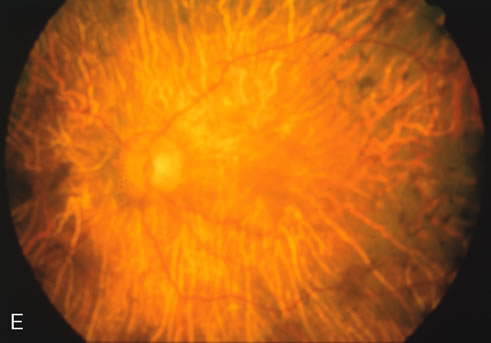

The carrier female with XLR RP, who has the golden tapetal sheen reflex, has normal FA findings. This suggests that the abnormal reflex is not due an abnormal pigment layer or deposition7 (Fig. 2A and B).

Fig. 2. Golden tapetal reflexes. There are three diseases in which there is an unusual golden reflex to the fundus: X-linked recessive RP in the carrier female, Oguchi's disease, and cone dystrophy. In all these diseases the angiogram is essentially normal, suggesting that this reflex is probably not related to pigment abnormalities. A, B. Carrier female of XLR retinitis pigmentosa. A golden scintillating reflex radiates from the macula. C, D. Oguchi's disease. A diffuse yellow metallic sheen is seen in the posterior pole (a pigmented chorioretinal lesion is an incidental finding). E, F. Progressive cone dystrophy. The typical bull's eye maculopathy is associated with a golden orange reflex.

In Oguchi's disease the hallmark fundus finding is a yellow metallic sheen (Fig. 2C). A similar sheen has been seen in progressive cone dystrophies and juvenile macular degeneration.7 In all these diseases the abnormal reflex does not affect the normal transmission of fluorescein dye (Fig. 2D). The normal FA suggests that, like findings in the carrier female in XLR RP, the abnormal retinal reflex in this disease is unrelated to pigment concentration or distribution.

Fluorescein angiography highlights observable fundus findings. In patients with a golden reflex the FA is normal (Fig. 2E, F) or shows a mild transmission hyperfluorescence.7